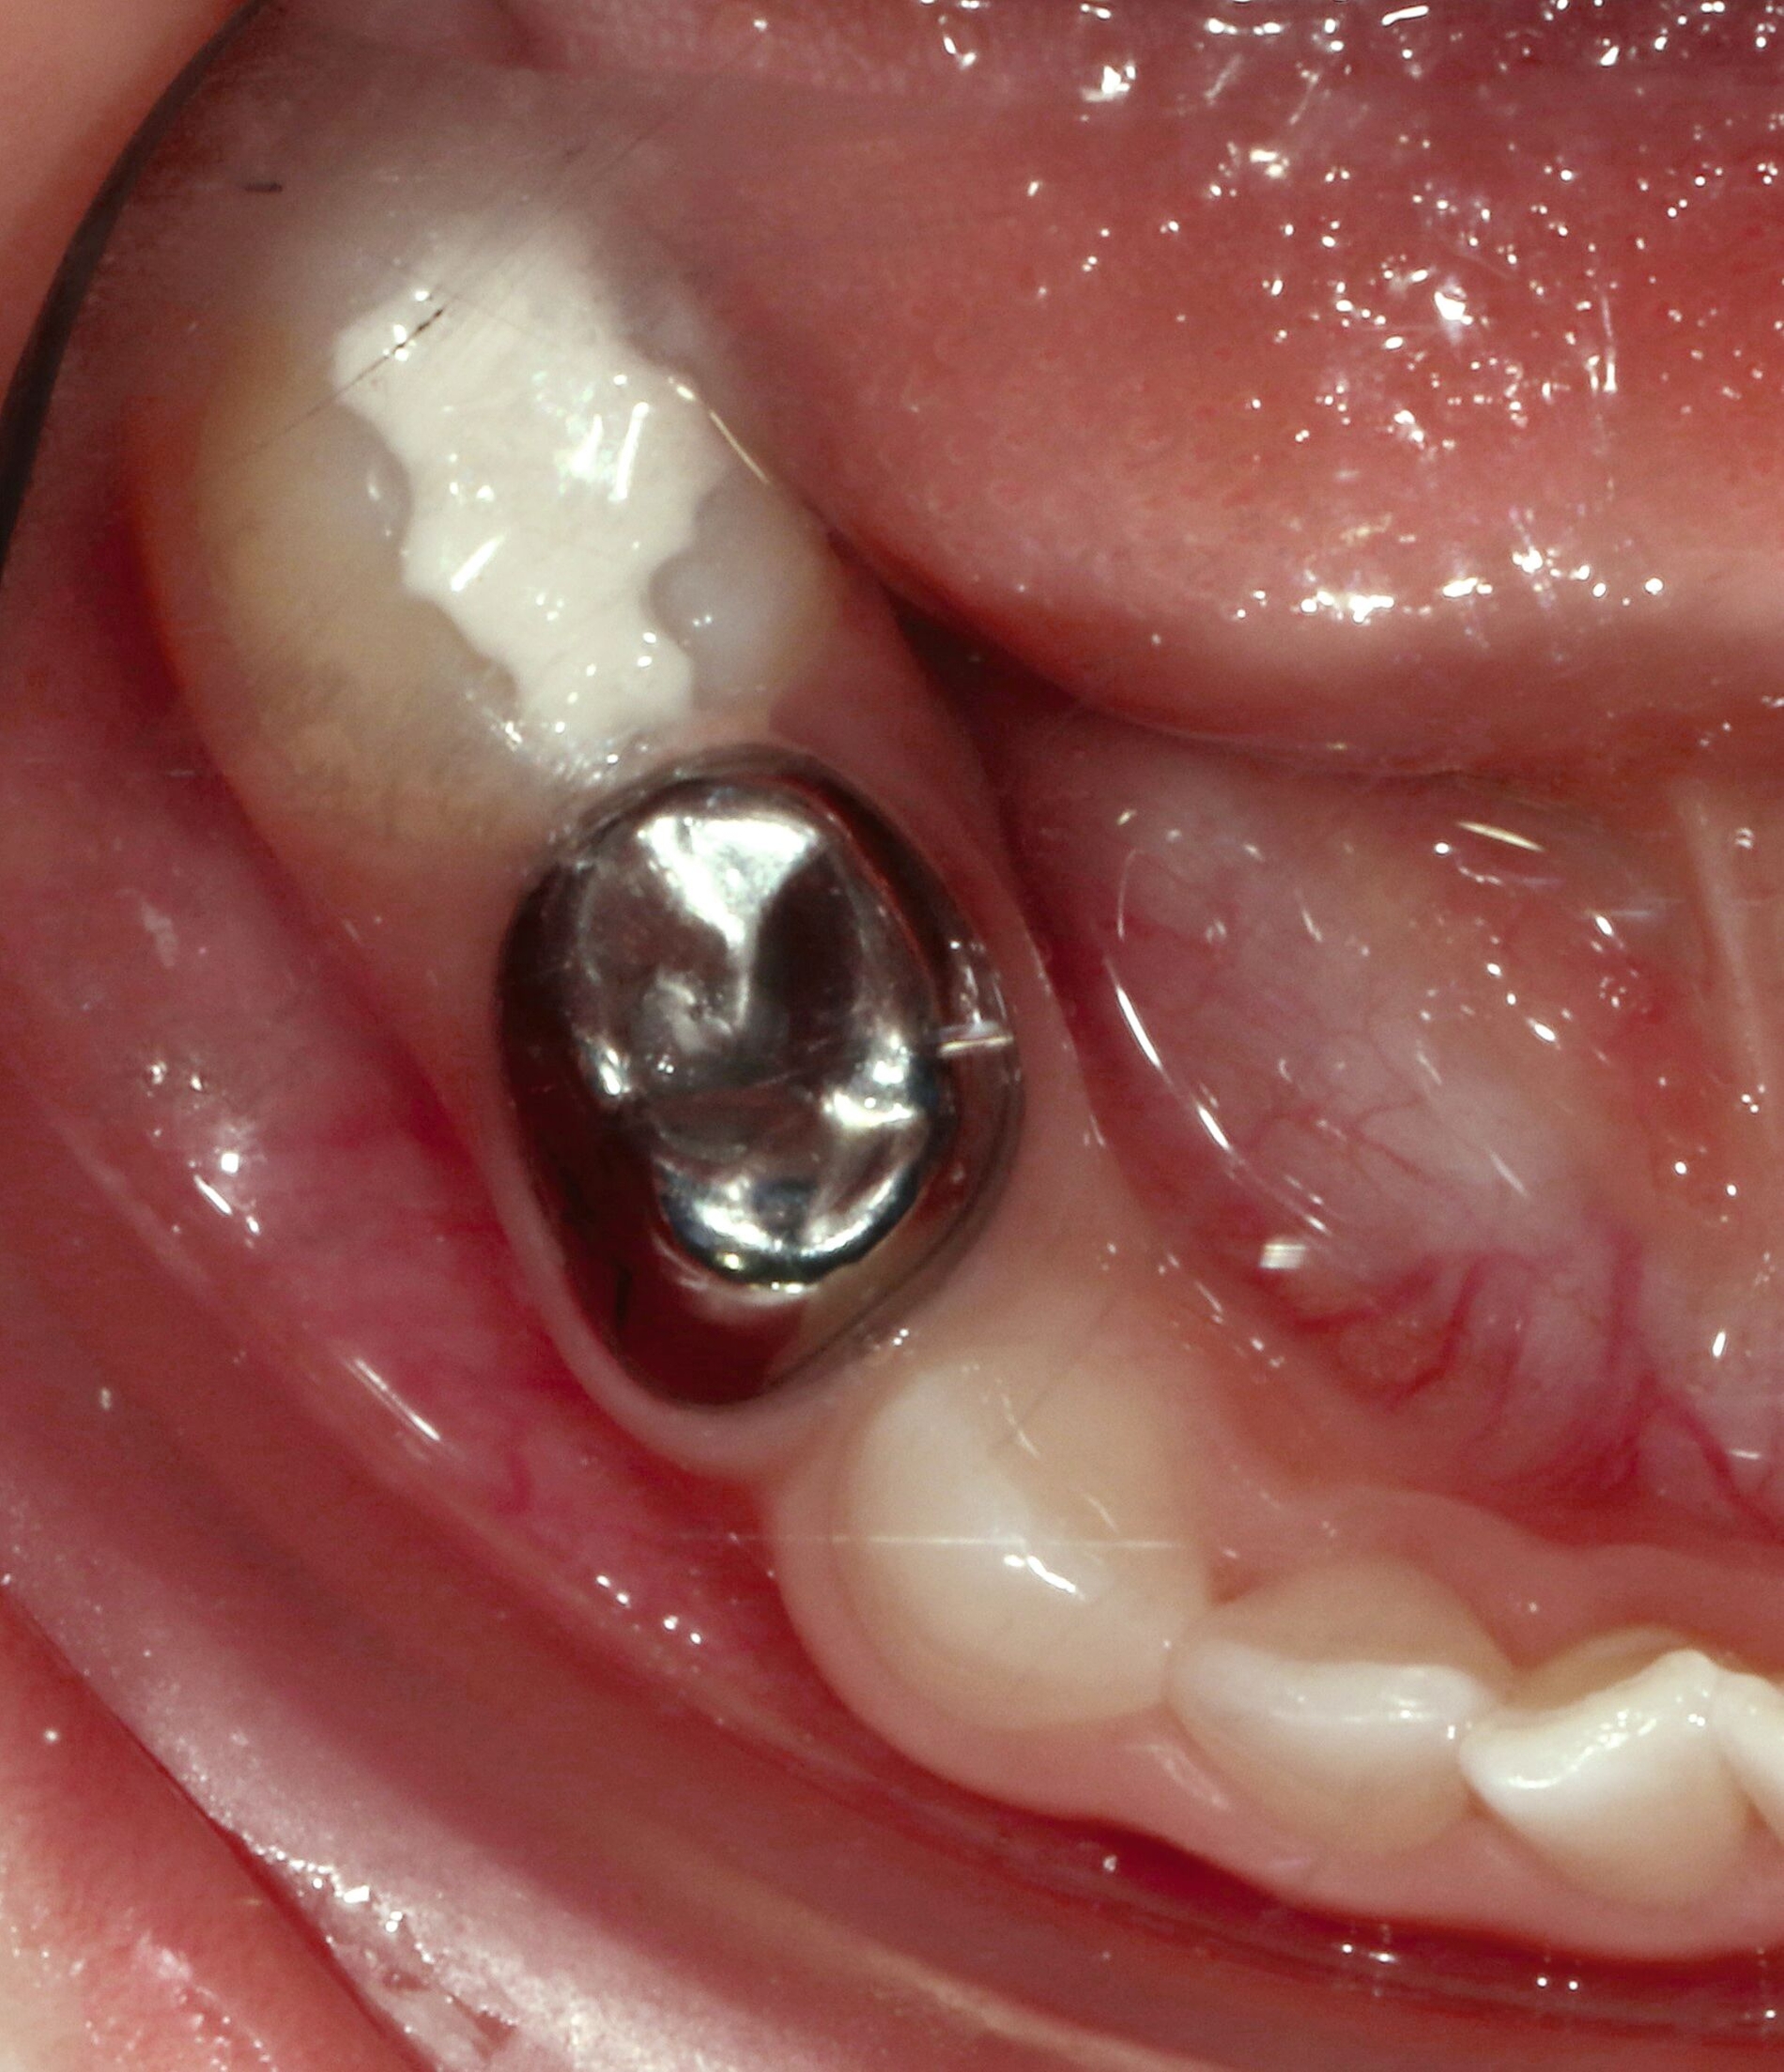

Bei der Behandlung von Patienten mit besonderen Bedürfnissen scheint sich der Schwerpunkt der präventiven und restaurativen Strategien zu verlagern, indem minimalinvasive Methoden wie SDF und die Hall-Technik eingesetzt werden (Abbildung 5). Minimalinvasive Therapien haben sich als geeignet und wirksam für die Behandlung von Kariesläsionen sowohl bei Milchzähnen als auch an bleibenden Zähnen erwiesen und reduzieren somit die Notwendigkeit von Eingriffen unter Vollnarkose [Molina et al., 2022].

Die Applikation von Silberfluorid ist einfach, gut akzeptiert und lindert erfolgreich Überempfindlichkeiten bei MIH, wie Studienergebnisse unserer Arbeitsgruppe zeigen [Ahmed et al., 2023; Ahmed et al., 2024]. Nachteilig ist jedoch die schwer vorhersagbare, aber mögliche dauerhafte Schwarzverfärbung der hypomineralisierten Bereiche. Hier sollte also in Abhängigkeit der Lokalisation und des Schweregrades der Hypersensibilitäten abgewogen werden, ob diese Technik direkt beim Erstbesuch oder gegebenenfalls doch nur bei persistierender Überempfindlichkeit bei einem der Recall-Besuche erfolgen sollte („SMART“ im Recallbesuch) (Abbildung 7). Sofern MIH-Läsionen hauptsächlich approximal liegen oder die MIH-Molaren so stark betroffen sind, dass unabhängig von der Initialbehandlung mittelfristig eine Kronenversorgung (zum Beispiel Stahlkrone) oder sogar eine Extraktion wahrscheinlich ist, wäre die Silberfluoridapplikation aufgrund der schnellen Wirkung eine probate Option - auch als SMART-Technik beim Erstbesuch.